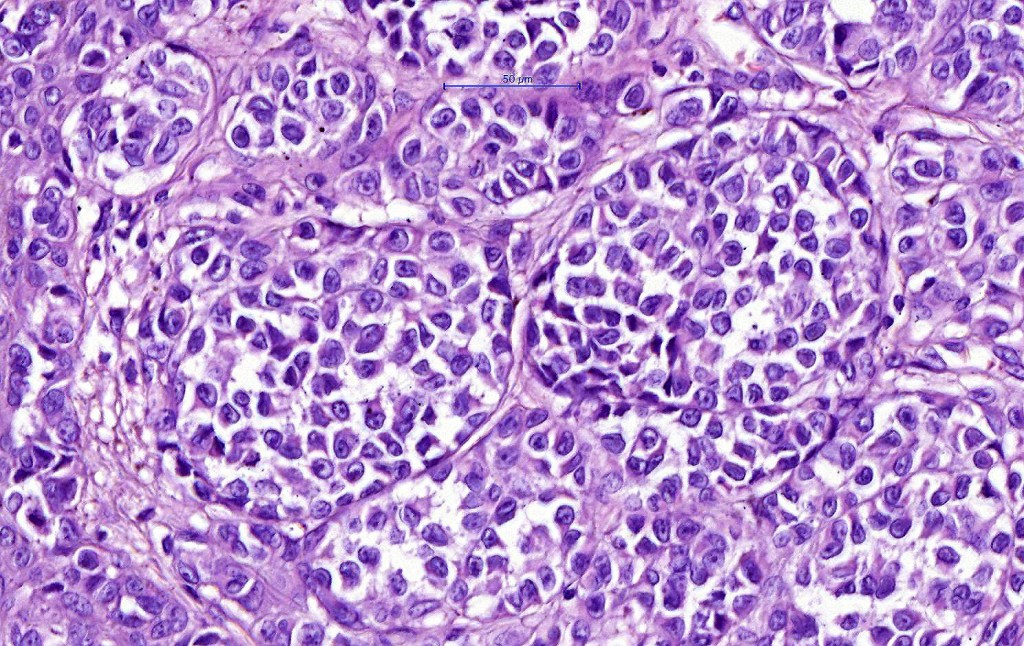

•Expansile nodules or diffuse

•Compression of connective tissue

•Mimics type-A cells, (lesions which mimic type B nevus cells are often classified as small cell melanoma, this is important as the differential diagnosis is very different- see separate blog)

•Subtle or not so subtle impaired maturation with depth (sometimes this is evident at scanning magnification)

•Subtle nucleolar prominence

•Subtle pleomorphism

•Mitoses invariable including often in the deep aspect